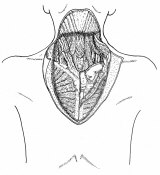

器械吻合器を用いた、咽頭部食道癌摘出後再建法

首の解剖の本と首っ引きで描きました。